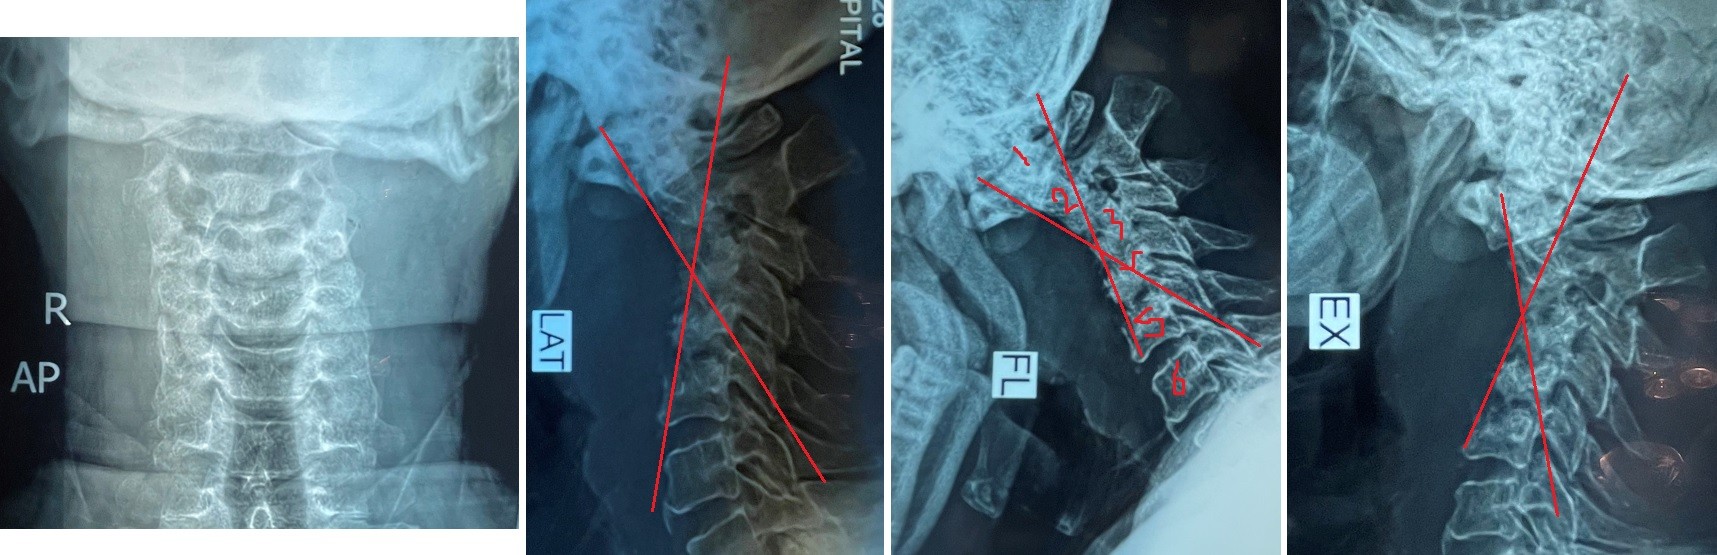

cervical vertebrae kyphosis repair